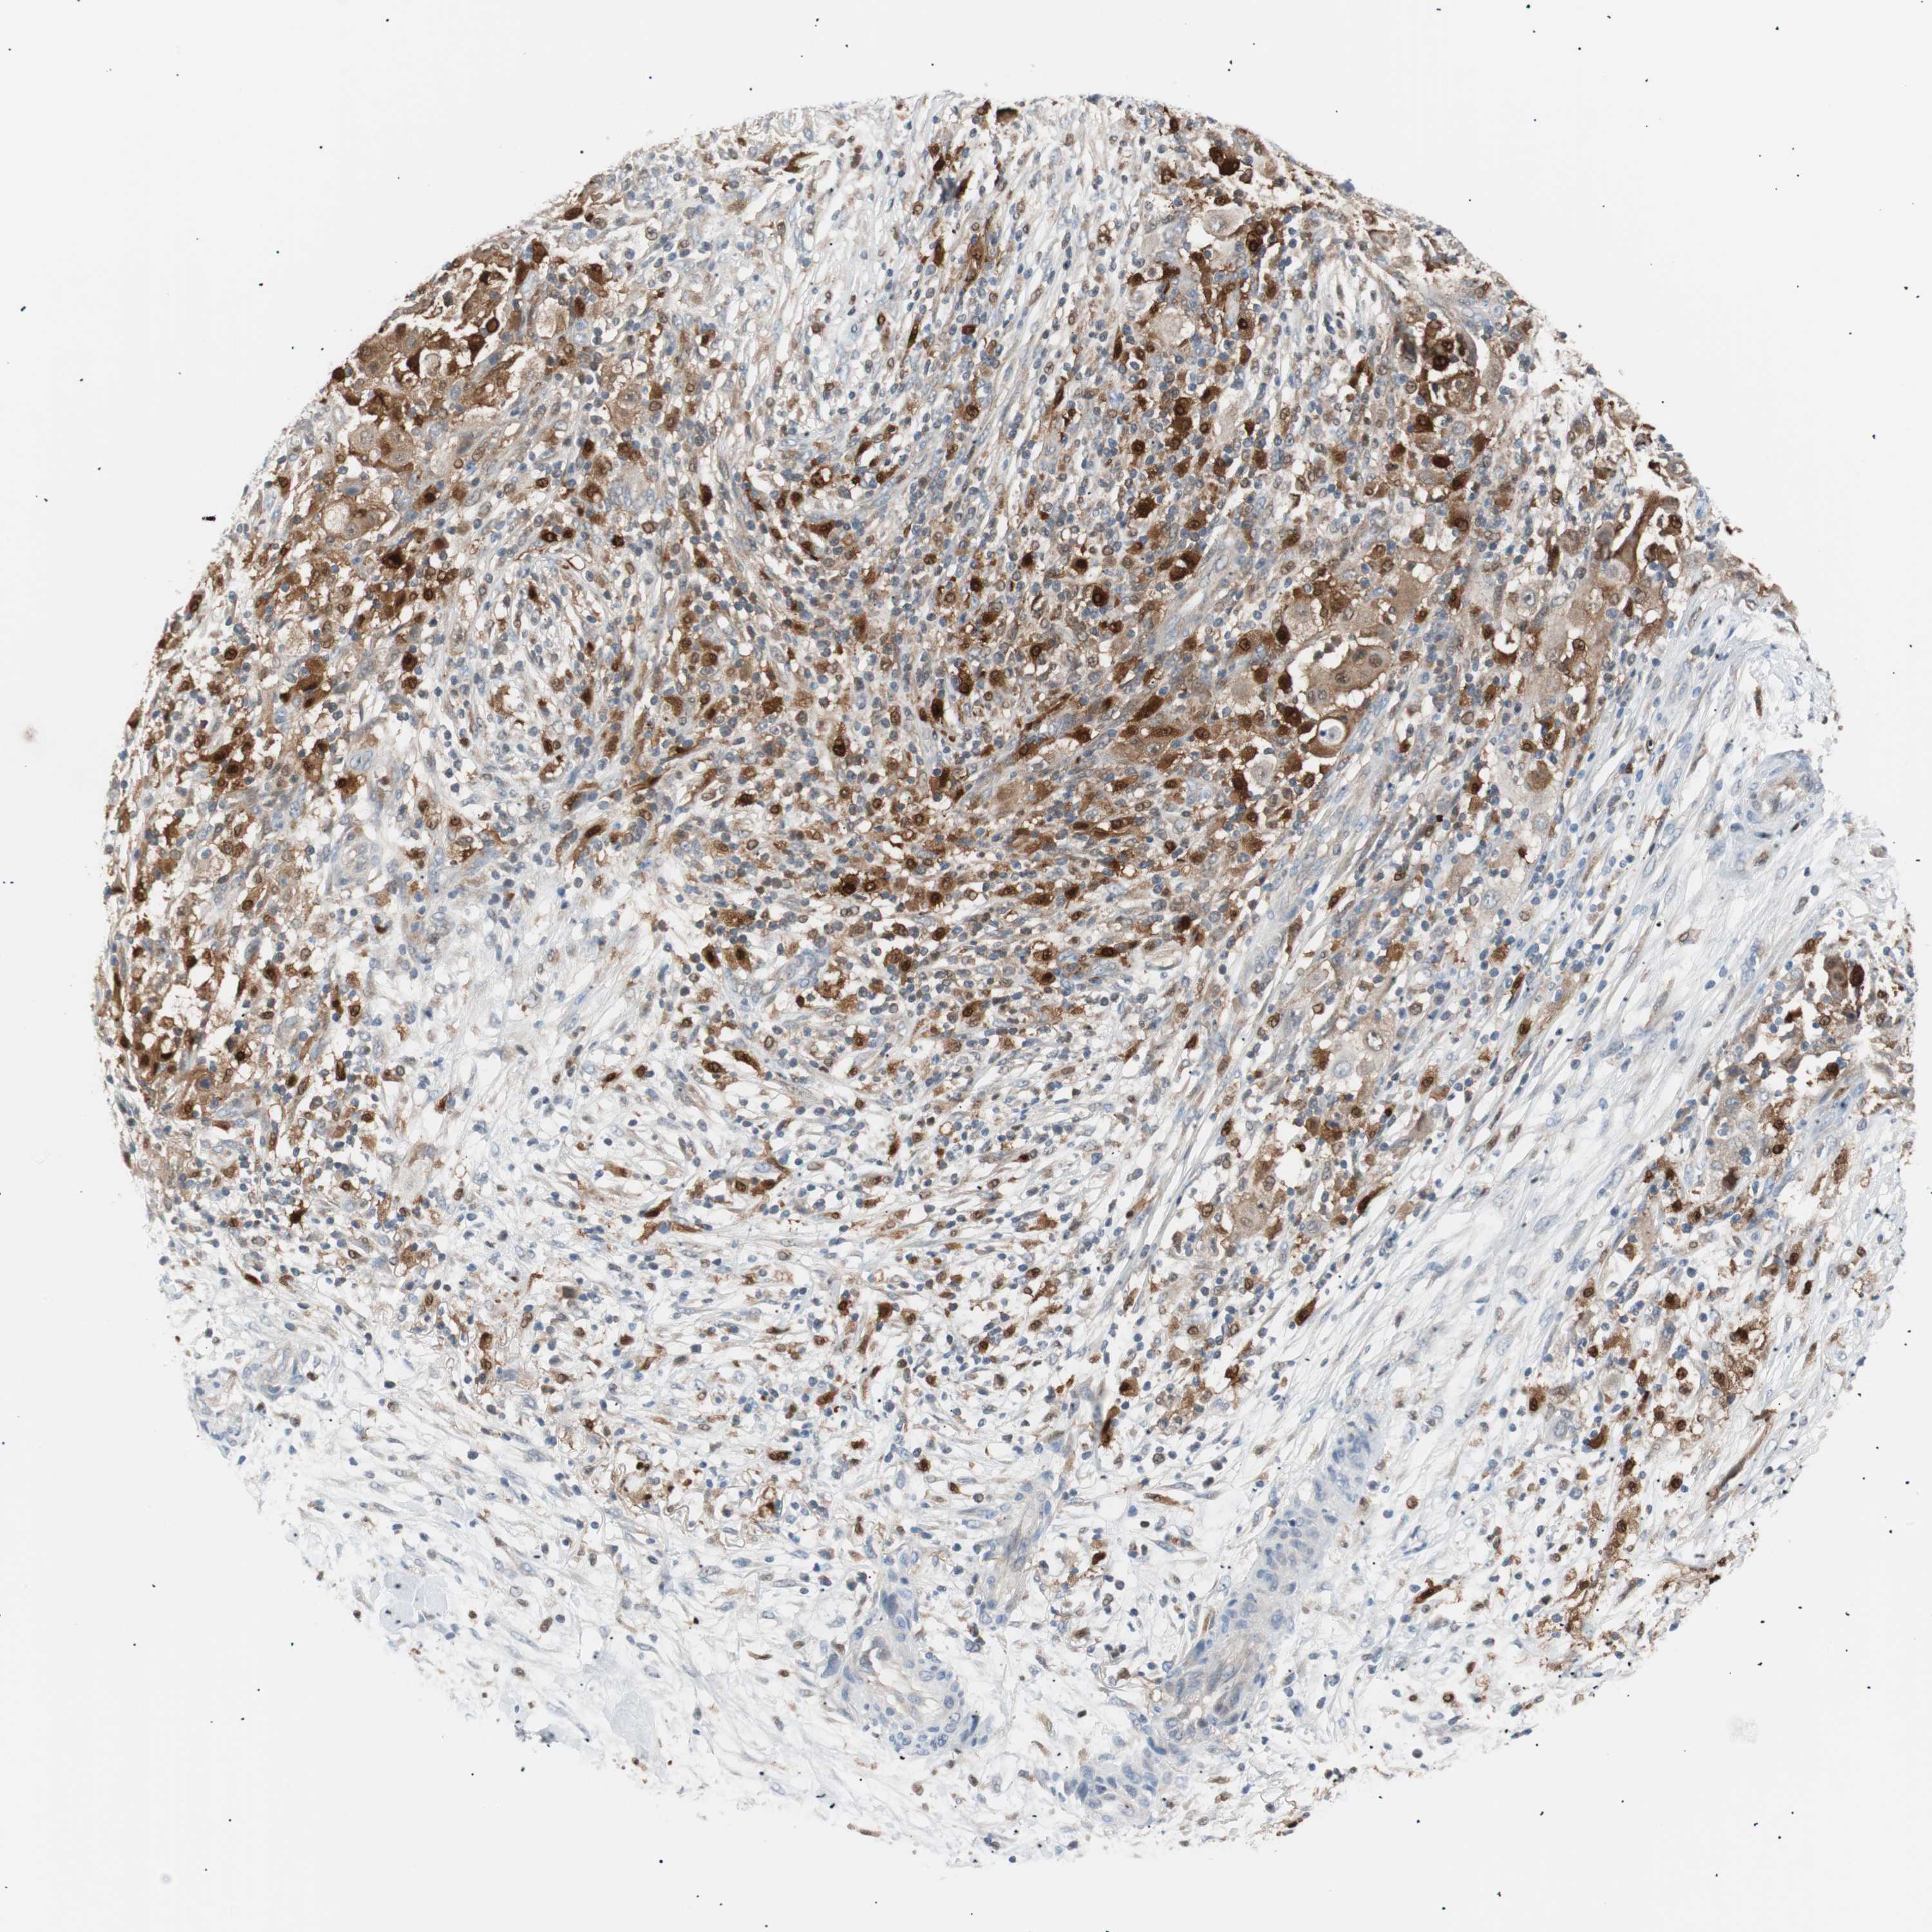

OVARIAN CANCER - Protein expressioni

A mouse-over function shows sample information and annotation data. Click on an image to view it in a full screen mode. Samples can be filtered based on level of antibody staining by selecting one or several of the following categories: high, medium, low and not detected. The assay and annotation is described here.

Note that samples used for immunohistochemistry by the Human Protein Atlas do not correspond to samples in the TCGA dataset.

Antibody stainingi

Antibody staining in the annotated cell types in the current human tissue is reported as not detected, low, medium, or high, based on conventional immunohistochemistry profiling in selected tissues. This score is based on the combination of the staining intensity and fraction of stained cells.

Each image is clickable and will lead to virtual microscopy that enables deeper exploration of all samples and also displays staining intensity scores, fraction scores and subcellular localization as well as patient and tissue information for each sample.

Antibody HPA003980

Antibody CAB007772

Staining

High

Medium

Low

Not detected

Intensity

Strong

Moderate

Weak

Negative

Quantity

>75%

75%-25%

<25%

None

Location

Nuclear

Cytoplasmic/membranous

Cytoplasmic/membranous,nuclear

Carcinoma, endometroid

Carcinoma, NOS

Cystadenocarcinoma, serous, NOS

Cystadenocarcinoma, mucinous, NOS